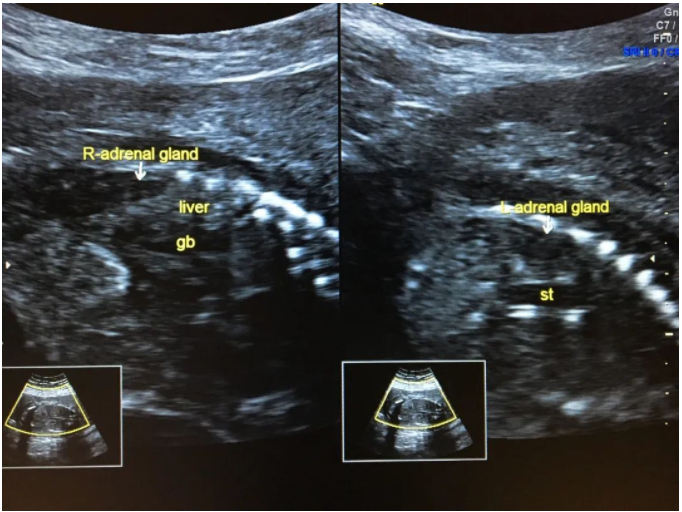

一、肾缺如表现为肾区无肾脏回声,肾上腺平卧。

上图示双肾缺如,肾上腺平卧。

上图示正常双肾及肾上腺。(R-adrenal gland/R-AD:右侧肾上腺,L-adrenal gland/L-AD:左侧肾上腺,RK:右肾,LK:左肾,liver:肝,st:胃)